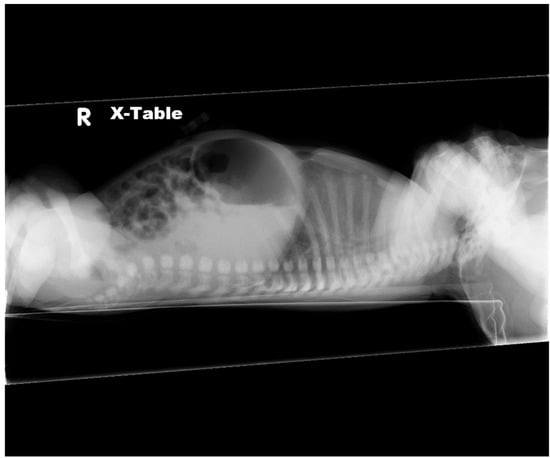

2.1. Case 1